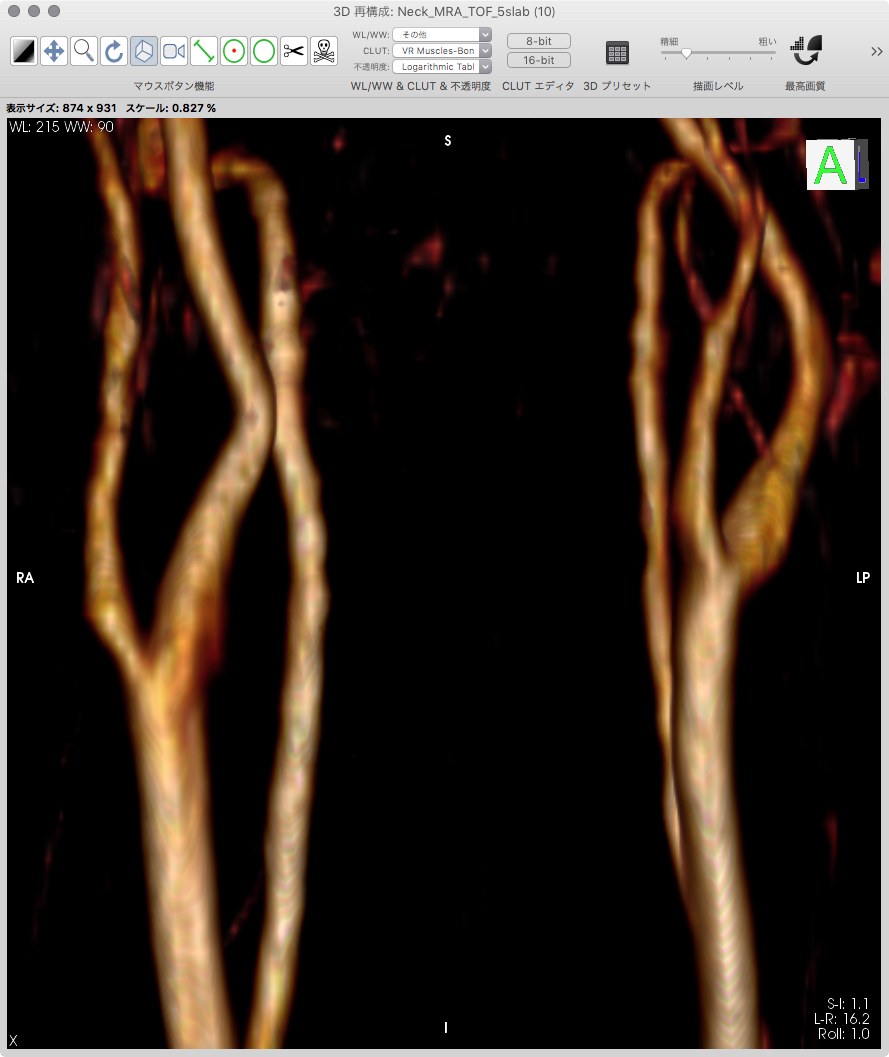

頚部MRA |

画像サンプル |